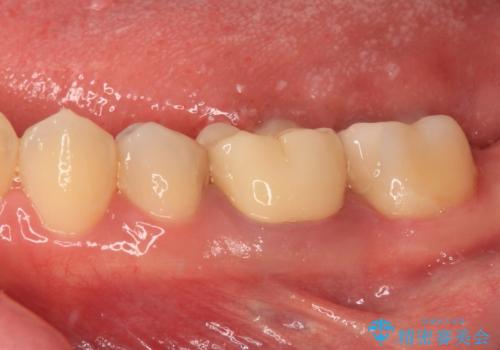

治療後はものが挟まりにくくなり、その上舌触りも良くなり、早く治療を始めておけばよかったとおっしゃっていました。